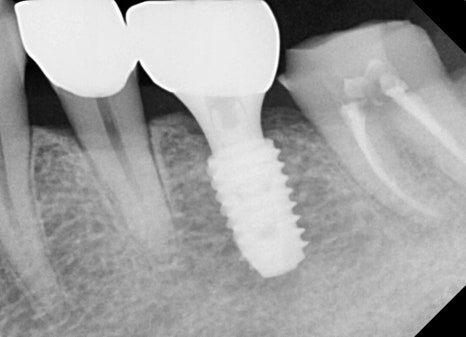

🖼️ 치료 후사진

오른쪽 사진: 신경치료가 완료된 치아와 임플란트가 잘 자리잡은 모습을 보여주는 부분 엑스레이입니다.

➡ 신경치료가 끝난 치아는 뿌리까지 약재로 잘 채워졌고, 그 위에 보철물(크라운)도 잘 씌워졌습니다.

➡ 빠졌던 어금니도 임플란트로 기능이 회복되어, 환자분은 씹는 힘과 편안함 모두 만족하셨습니다.